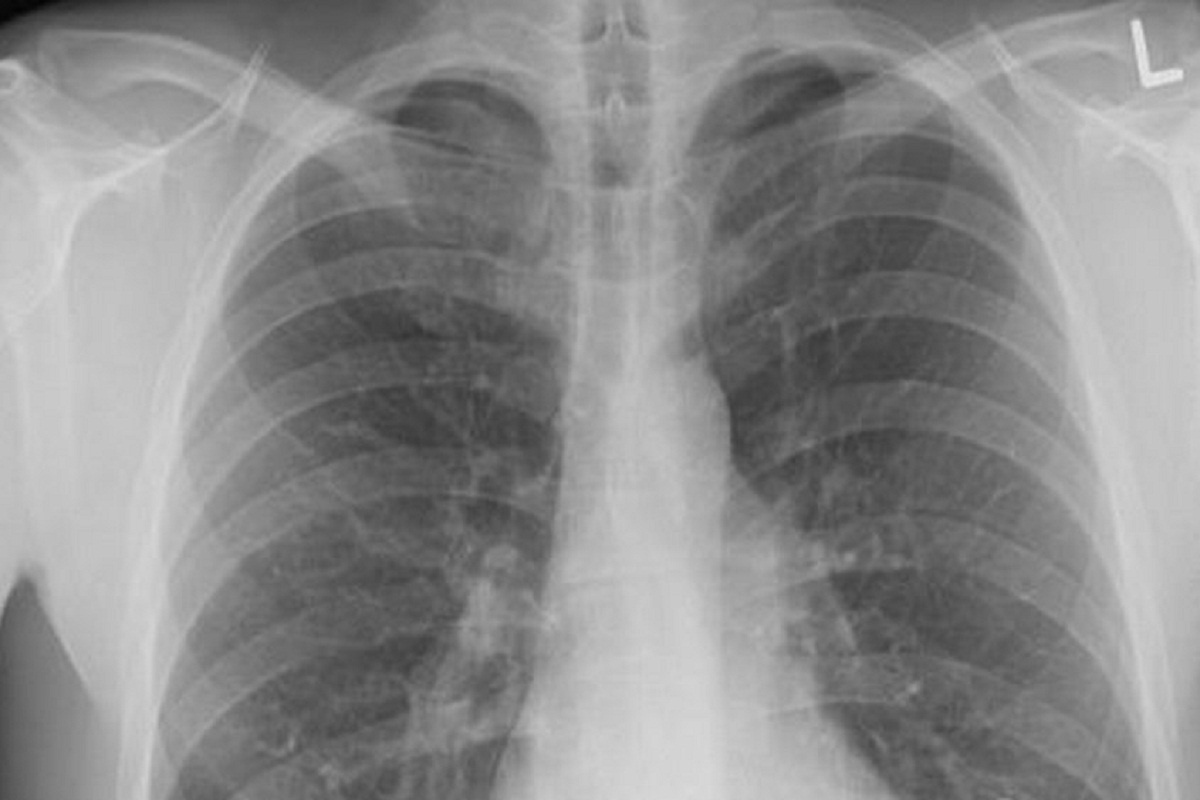

В России отмечен рост заболеваемости микоплазменной пневмонией, которую также называют внебольничной. Роспотребнадзор ранее заявил, что ситуация с заболеваемостью находится под контролем, поэтому причин для сильного беспокойства у населения быть не должно.

Кроме того, отметил инфекционист Владимир Чуланов, микоплазменная пневмония отличается относительно легким течением. В разговоре с ТАСС он отметил, что чаще всего больным не требуется госпитализация, поскольку этот вид воспаления легких имеет благоприятный прогноз среди всех групп населения.

Несмотря на это, микоплазменная пневмония не пройдет сама по себе, поэтому требует соответствующего лечения, которое должен назначить врач. Обращаться к специалистам стоит, если наблюдаются приступообразный сухой кашель, общая слабость, головная боль, повышение температуры тела, боль в горле и мышцах.